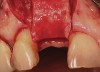

A 53-year-old woman presented with a failing implant in the No. 7 site (Figure 12 and Figure 13). Her desire was to eliminate infection and preserve esthetics. A team effort between the periodontist and restorative dentist to advocate for additional restorative dentistry as well as manage the patient’s expectation of time required was essential. In addition, the patient needed to have realistic expectations of a compromised outcome. Both the restorative dentist and the periodontist informed the patient about the difficulty of achieving this with acceptable esthetic results. Mutual emotional and technical support was required to successfully complete this case, from initial grafting of the defect to placement of anterior restorations (Figure 14 through Figure 23).